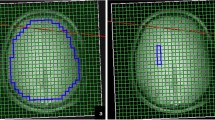

MRSI processing

MRSI data were processed using the Metabolite Imaging Data Analysis System (MIDAS) software [21]. The following were applied during preprocessing: spatial reconstruction, B0 shift correction, interpolation to 64 × 64 × 32 points, and smoothing with Gaussian kernel (5 mm in plane, 7 mm through plane). The FITT2 module was used to carry out spectral fitting with Gaussian line shapes. Metabolite maps were normalized to institutional units using tissue water from an interleaved non-water-suppressed MRSI acquisition. Images were registered to each subject’s high-resolution T1-weighted image and the tissue distribution for spectroscopic images was determined following segmentation of the T1-weighted images with FSL/FAST [22]. A non-linear spatial transform was applied to the metabolite maps and tissue distribution images for registration to 2 mm Montreal Neurological Institute (MNI) space. A modified version of the Automated Anatomical Labeling (AAL) atlas [23] was used to delineate 47 regions of interest (ROIs) for statistical comparisons between groups.

Main results

There were no significant MRSI outcome differences between groups for any brain region at the p < 0.0023 threshold. Maps of the average CHO/CR ratios in the RA and control group are visualized in Fig. 2. Results for all group contrasts can be found in Online Resource 2.